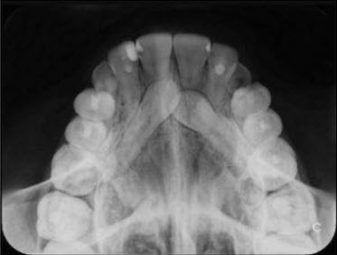

Oclusales

Son también pequeñas radiografías aunque en este caso la placa es un poco más grande y es la placa la que se muerde entre la arcada superior y la arcada inferior. El tubo de rayos X se coloca casi perpendicular a la placa y de esta manera se valoran dientes incluidos y su posición. Los dientes incluidos son los que no han aparecido en la boca, y se encuentran “escondidos”.

Actualmente este tipo de radiografía no se usa demasiado, ya que hoy día con los aparatos en 3D, escáner, nos permiten una exacta valoración de la posición.